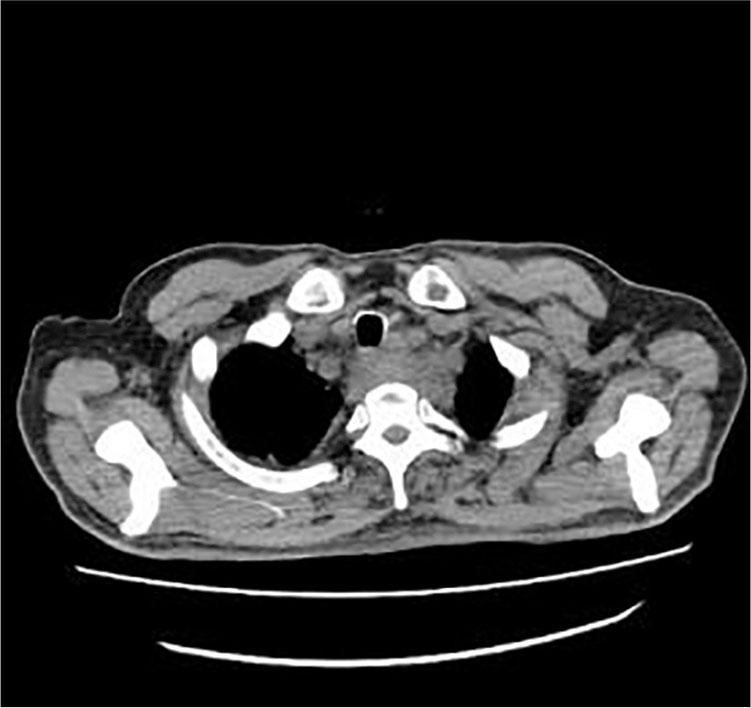

On September 23, 2016, a 56-year-old man consulted the emergency department for 7 days with unknown fever. The highest temperature was 38.5°C. Blood tests were as follows: WBC 7.75 × 109/L, NEUT 76.94%, CRP 120.57 mg/L, and procalcitonin 0.325 ng/ml. Posterior superior mediastinal masses with thickened adjacent esophagus wall and bilateral pleural effusion were revealed by thoracic computed tomography (CT) scan (Figure 1). A 1.0 cm × 2.0 cm protuberant mass was found in the left wall of the esophagus at 20 cm from the incisors by the gastric endoscopy (Figure 2). Endoscopic biopsy shows a chronic active inflammation with ulcer and granulation tissue proliferation. Examine the medical history in detail at that moment, the patient was diagnosed with an odynophagia and admitted that he had accidentally swallowed a fishbone 2 months ago. Taken together, the patient was diagnosed with secondary mediastinitis due to esophagus perforation caused by the ingestion of fishbone. The patient had been treated moxifloxacin intravenously for 15 days, and then he was discharged without fever. Obvious back pain and decreased muscle strength began on the 7th day after discharge. On November 10, he had a Magnetic resonance (MR) of the thoracic vertebra, and the result was C7/T1 centrum infection and paravertebral abscess (Figure 3). The surgical intervention had been performed 4 days later. Consequently, the back pain disappeared, the muscle strength recovered, and an MR reexamination showed the patient recovered completely (Figure 4).

Figure 2

The gastric endoscopy result.